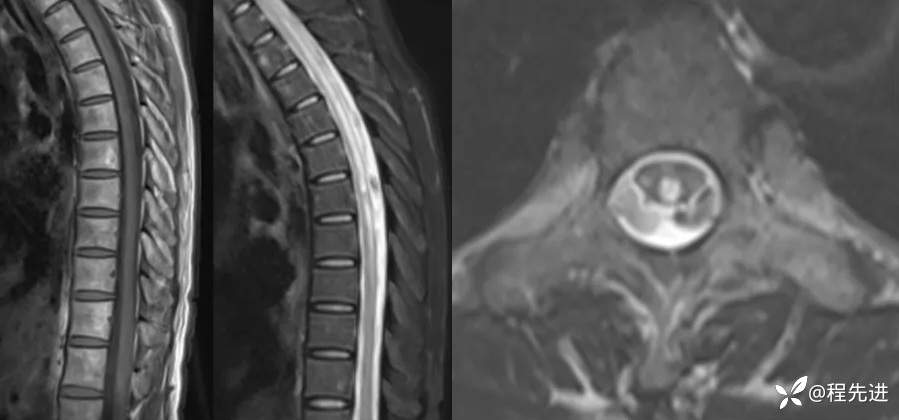

胸椎MRI平扫: